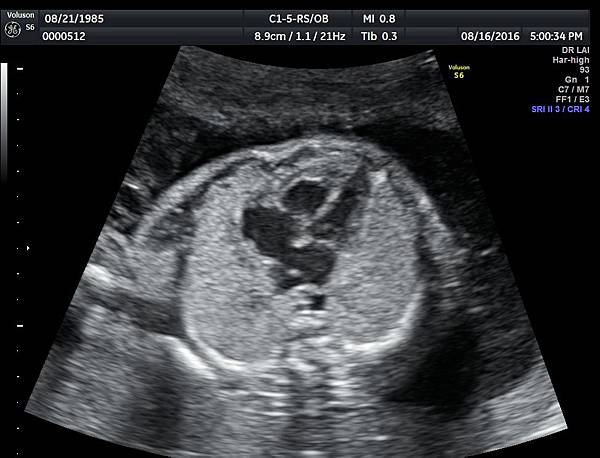

我看肺靜脈的心路歷程可以分成三個階段,第一個階段是用gray scale(黑白)看到左右肺靜脈下行支回到左心房(附圖 1.2.),第二個階段是用flow(彩色)看到左右肺靜脈回到左心房(附圖 3.4.),第三階段是同時要看到黑白和彩色的左右肺靜脈回到左心房,為什麼只有看flow(彩色)不安全呢?因為右肺靜脈的flow有時候是假影,為何會看到假影?因為右心房到左心房的flow overlapping(重疊)造成的(附圖 5.),如何判斷是假影,只要關掉flow看黑白的即可證明右肺靜脈沒有進入左心房(附圖 6.)。

如果同時看到左右肺靜脈進入左心房,這種誤判的機率下降很多,如果只能看到一條肺靜脈的血流,我會選擇左肺靜脈(附圖 7.8.),因為左肺靜脈的血流比較不會被overlapping,最安全的方法是黑白和彩色都看到左右肺靜脈進入左心房,只是需要胎兒姿勢配合,當然孕婦的體重也是需要考量的因素。